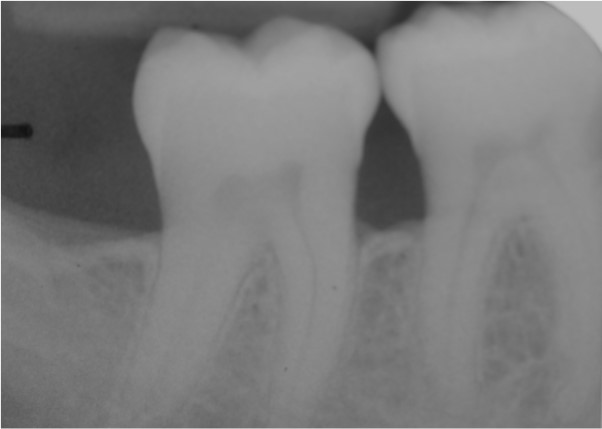

Radiographic view before periodontal regenerative therapy with Straumann® Emdogain®. A deep intrabony defect appeared mesially and distally on the left mandibular first premolar. Pre-surgical probing measured 8 mm. The defect morphology presented as well-contained.